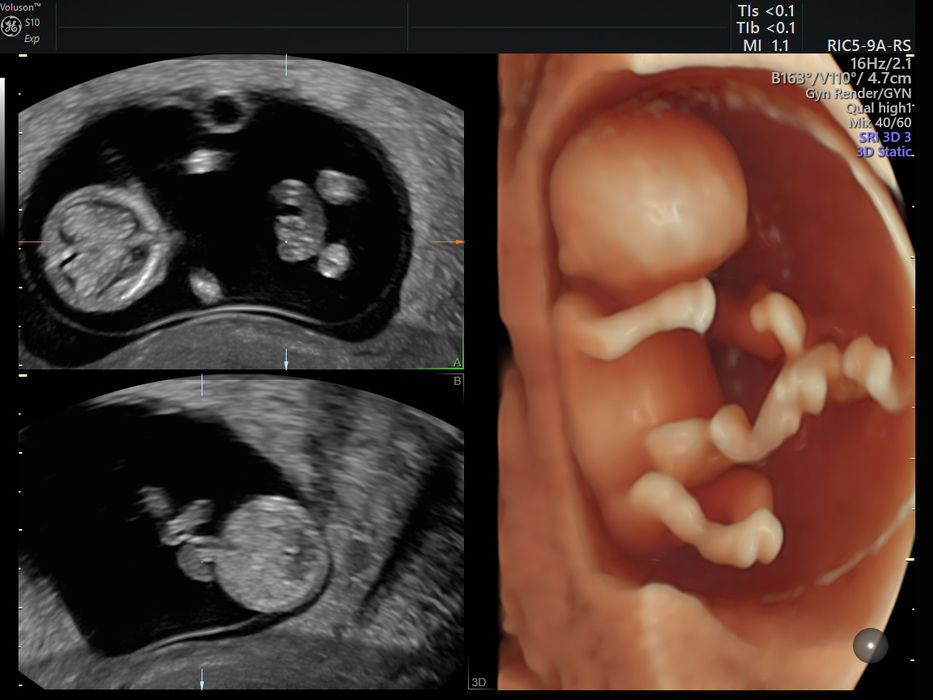

Voluson™ S10 je pokročilý ultrazvukový systém pro gynekologicko-porodnickou praxi poskytující vysokou kvalitu zobrazení.

Voluson™ S10 od GE Healthcare s novou systémovou architekturou Radiance Technology přináší nový standard v OB/GYN zobrazení s lepší prostorovou rozlišovací schopností, vyšší rychlostí a větší flexibilitou vyšetřování. Tento systém s nejnovějšími technologiemi je přímý nástupce prémiových přístrojů předchozí generace E-series. Jedná se o pokročilý přístroj pro gynekologicko-porodnickou praxi, který zároveň představuje velmi dobrou investici pro lékaře, kteří hledají spolehlivé a dlouhodobé řešení s vysokou kvalitou zobrazení ve všech modalitách. maximálním výkonem využívá osvědčenou technologii Voluson přístrojů s vylepšením v oblasti automatizace, produktivity. Tento přístroj posouvá hranice zobrazení ještě výše.

Technologie HDlive pro realistické 3D/4D zobrazení